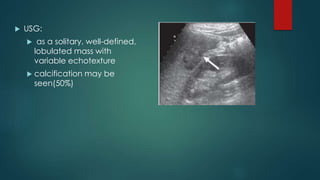

 USG:

 as a solitary, well-defined,

lobulated mass with

variable echotexture

 calcification may be

seen(50%)